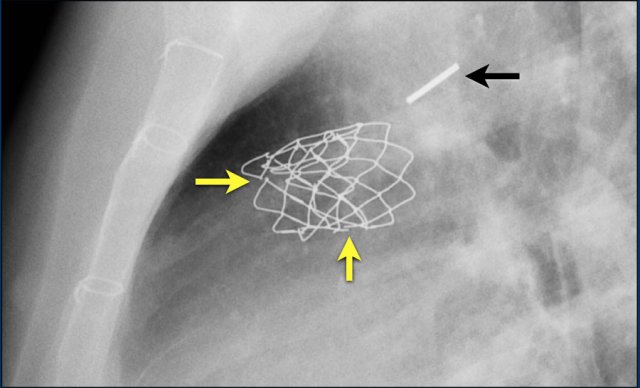

Here a lateral view of a child with an ASD and an Amplatz closure device.

A lateral view of a child with an ASD and an Umbrella Rashkind closure device.